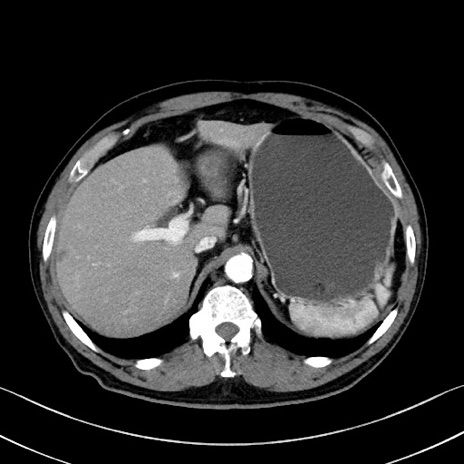

症例35(横断像)

【症例】70歳代 男性

【主訴】腹部膨満、嘔吐

【現病歴】昨日より腹部膨満感出現。本日増悪し、仙痛出現。嘔吐あり、受診。

【既往歴】糖尿病、胆摘後

【身体所見】BP 149/80mmHg、HR 74/min、BT 35.9℃、腹部:膨満、軟、圧痛なし。腸雑音減弱あり。上腹部正中切開瘢痕あり。

【データ】WBC 13500、CRP 1.72